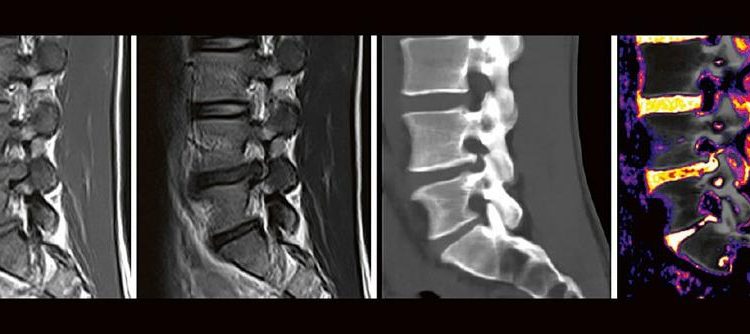

Professor Dr. med. Matthias PumbergerPD Dr. med. Torsten Diekhoff Die Dual-Energy-Computertomographie (DECT) hat für viele klinische Anwendungen bereits Einzug in die Praxis genommen. Für die Behandlung von Wirbelsäulenerkrankungen sind besonders die Darstellung von Knochenmarkveränderungen (z. B. bei osteoporotischen Frakturen) und der Bandscheibe (z. B. bei Bandscheibenvorfällen) interessant und werden intensiv beforscht. Hierdurch versprechen wir uns […]